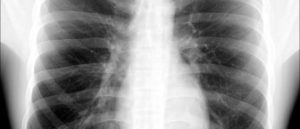

Метатуберкулезный цирроз

Метатуберкулезный цирроз одного или обоих легких проявляется их уменьшением в размерах, неоднородностью их структуры и расширением бронхов с формированием бронхоэктаз. Также выявляются специфические признаки цирроза в виде кальцинированных очагов в зоне поражения или обызвествления лимфатических узлов.

Чаще всего это заболевание, как и другие метатуберкулезные изменения, выявляется лишь при рентгенологическом исследовании и никак не беспокоит больного.

Метатуберкулезный цирроз легких на рентгене